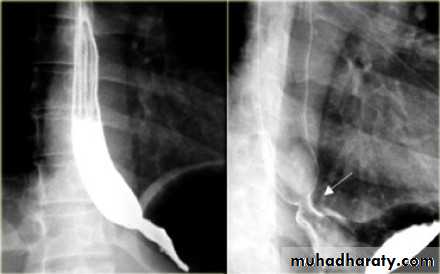

5. barium swallow which shows reflux of the gastric content to the esophagus.